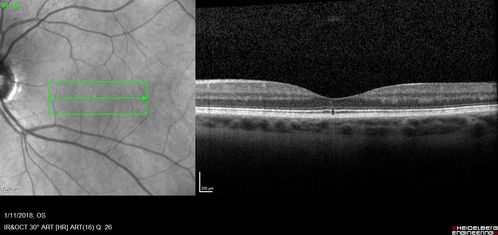

Foveal Red Spot Syndrome Left Eye

She noticed on covering the right eye that she had distortion off center in the left eye a few weeks ago.  She had a temporal paracentral scotoma intermittently visible on the eye examination.  She does notice that the left eye is not as good as the right eye now that it has been brought to her attention.  She has every now and then a little twitch in the left eye.  She has no pain on eye motion.

VA OD: sc20/20 NccJ1+

VA OS: sc20/20-1